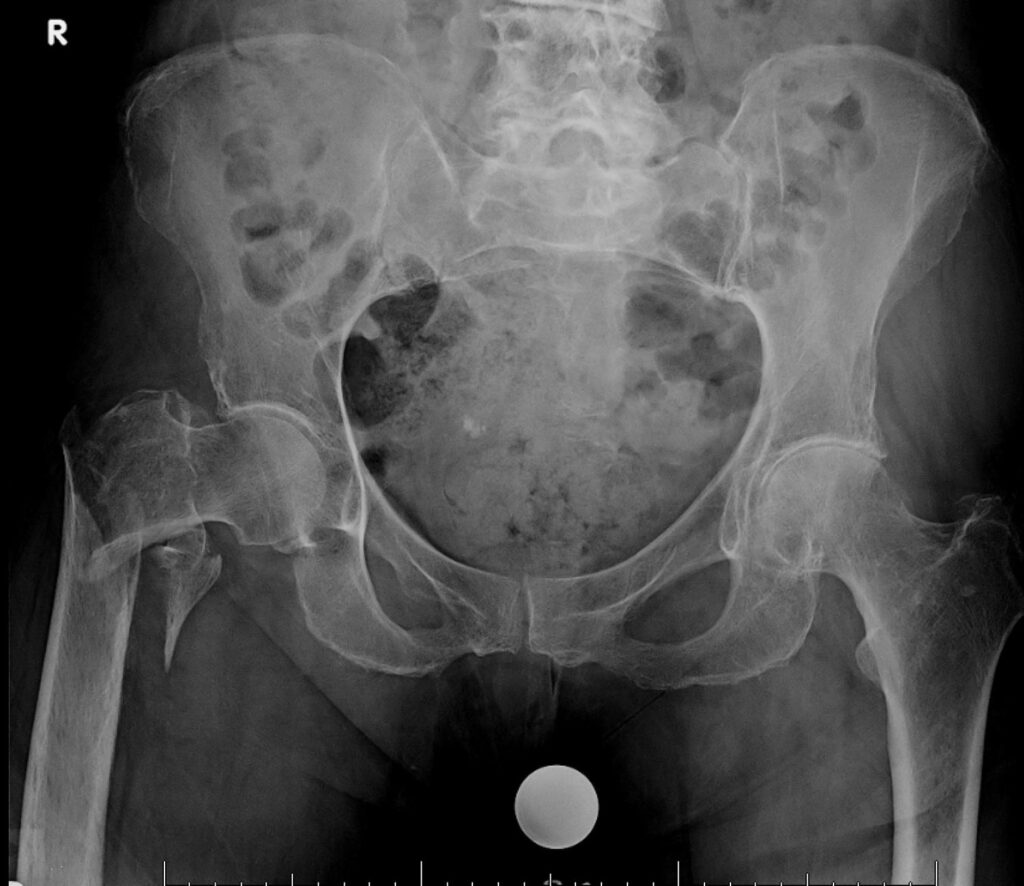

A 72-year-old woman presents to the emergency department after a fall at home. She complains of severe pain in her right hip and is unable to bear weight on the affected leg. On examination, the right lower limb is shortened, externally rotated, and there is tenderness over the hip region. An X-ray of the pelvis and right hip (see image) is obtained.

Which of the following best describes the diagnosis?

A) Intertrochanteric fracture of the femur

B) Femoral neck fracture

C) Acetabular fracture

D) Pubic ramus fracture

E) Hip dislocation